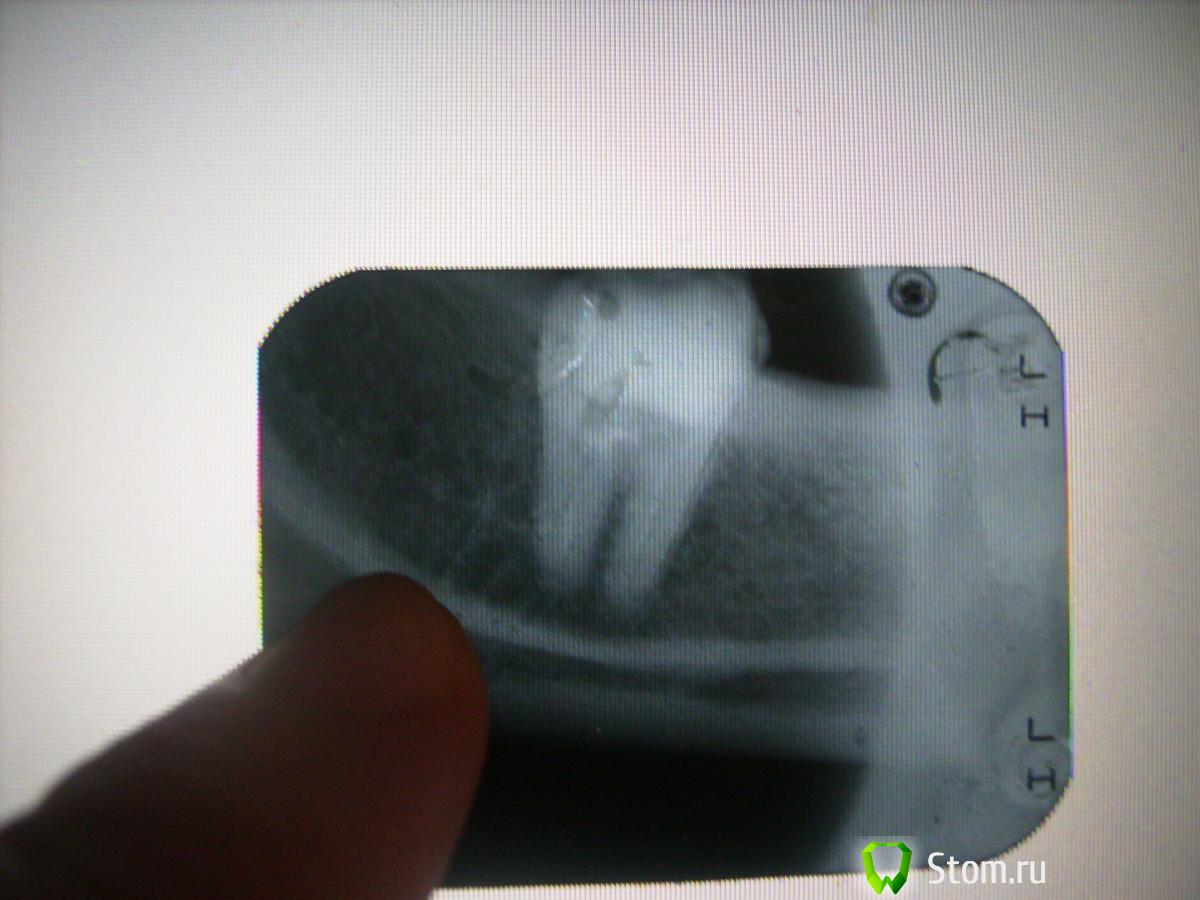

болящая Опубликовано 8 января, 2012 Автор Поделиться Опубликовано 8 января, 2012 Вот снимок. Ссылка на комментарий

juli63 Опубликовано 8 января, 2012 Поделиться Опубликовано 8 января, 2012 раздолбали зуб конечно неслабо, плохое лечение корневого канала. качество снимка не очень хорошее для детального рассмотрения, но мне кажется, что инструмент в канале сломан. может трещина есть уже, если нет то будет однозначно. в долгосрочном прогнозе-зуб не жилец. Ссылка на комментарий

болящая Опубликовано 8 января, 2012 Автор Поделиться Опубликовано 8 января, 2012 раздолбали зуб конечно неслабо, плохое лечение корневого канала. качество снимка не очень хорошее для детального рассмотрения, но мне кажется, что инструмент в канале сломан. может трещина есть уже, если нет то будет однозначно. в долгосрочном прогнозе-зуб не жилец.Вы меня убили! Это был ЖИВОЙ зуб,без полости,с поверхностным пришеечным кариесом. Если и он кандидат в морг,то останется только 3-ка! как не хочется съемник в 40 лет.Может Вы мне поможете,у меня вопрос про имплантаты при ревматоидном артрите повис в воздухе(тема в хирургии) Ссылка на комментарий